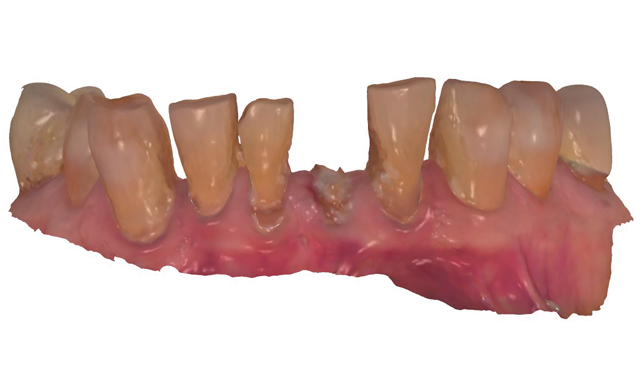

An 88-year-old man presented for restoration of tooth #25, which was fractured and had been endodontically treated (Fig. 1). A thorough intraoral and radiographic examination was performed, which revealed damage to the remaining anterior mandibular teeth incurred over the years as a result of scaling and curettage (Fig. 2). This damage to the

root surface of the lower incisors-which was visible on the radiograph (Fig. 3)-is known as “Riffle-ization.” Described by Dr. Riffle as a technique for removing every last bit of calculus during repeated root scaling, what is now known as “Riffle-izing," ultimately-over the years-changes the shape of the neck of the tooth to resemble an hour glass.

Therefore, based on the clinical and visual evaluation, the preferred treatment would be to restore the fractured #25 with a post and crown and four splinted crowns to restore the anatomy of the four incisors and increase their resistance to both mobility and fracture.